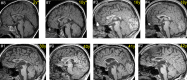

Results: Seven out of nine males with ZDHHC9 mutations had been diagnosed with epilepsy, exceeding epilepsy risk in XLID comparison subjects (P = 0.01). Seizure histories and EEG features amongst ZDHHC9 mutation cases shared characteristics with rolandic epilepsy (RE). Specific cognitive deficits differentiated males with ZDHHC9 mutations from XLID comparison subjects and converged with reported linguistic and nonlinguistic deficits in idiopathic RE: impaired oromotor control, reduced verbal fluency, and impaired inhibitory control on visual attention tasks. Consistent neuroanatomical abnormalities included thalamic and striatal volume reductions and hypoplasia of the corpus callosum.